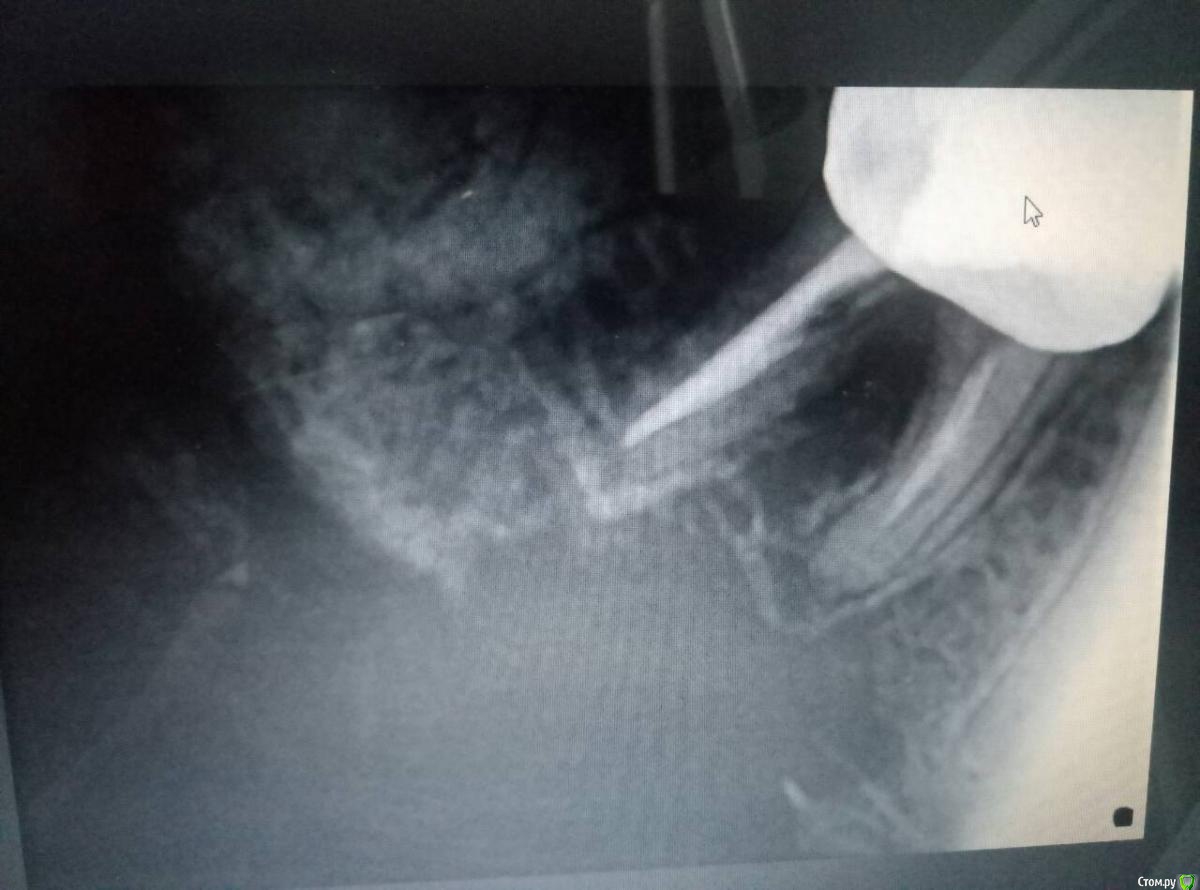

Инна2106 Опубликовано 27 июля, 2018 Поделиться Опубликовано 27 июля, 2018 (изменено) Добрый день.Прошу помочь определить в чем может быть причина ситуации с зубом которая длиться уже две недели.Началось все в ночь 13 августа проснулась от боли в одном участке нижней челюсти, именно не зубе, а челюсти, боль не острая, а тупая ноющая. Встала, походила все прошло. Весь день ничего не болело. В ночь все повторилось уже дважды просыпалась от боли, не определенного зуба, а низа левой челюсти. Для снятия боли достаточно было просто походить в течении 5 минут, все успокаивалось.На следующий день пошла к врачу, сделал снимок, осмотрел, сказал, что есть небольшая гранулема под шестым зубом под коронкой из-за не до конца запломбированного канала, но это как оказалось старая проблема, определялась еще на ортопанораме зимой. Но по его словам она не может давать такого рода болей. Ночью не спала вообще, четыре раза вставала от болей, причем стоило только принять горизонтальное положение и начиналась ноющая боль в нижней челюсти слева, и потом верхней челюсти слева. Суть в том что боли появлялись именно когда ложилась, не важно днем или ночью, пока ходишь, сидишь ничего не беспокоило. Снова поехала на прием к врачу, сделал много проб, и воздухом и нитью, подозревал трещину по снимку рядом в зубе под пломбой, но сказал нить не цепляется и не рвется значит ее нет, но вскрывать этот зуб не смысла так как на простукивание все было спокойно и сверху и снизу. Десна все розовые, кровоточивости нет. Через три дня поехала к другому врачу сделал свой снимок, предположил как вариант что восьмерка может двигать зубной ряд оттуда и боль, но сама восьмерка абсолютно спокойна, не болит, нет отечности десны. Его заключение, что причина в троичном нерве, а не в зубах. До этого по рекомендации первого врача принимала Азитромицин 3 дня и Нимесил не помогло. Начала пить Нейродикловит (диклофенак с витаминами группы В) и наконец-то начала ночью спать, но с понедельника 23 июля начал болеть зуб при накусывании рядом с коронкой (семерка), я на эту сторону и так не ем уже две недели, почувствовала боль при пережевывании пищи. когда верхних зуб попадал на нижний, попробовала постучать ложкой и ощутила боль в семерке снизу. В среду поехала к третьему врачу, он сделал пришлифовку семерки нижней с верхней так как нагрузка на зуб неправильно распределялась на одно сторону, порекомендовал попить Нимесил и наблюдать.Суть в том, что на данный момент исчезли боли в горизонтальном положении, но не могу жевать и есть нормально, сам зуб не болит, но если попробовать накусить слегка зубочистку на семерку появляется боль, отпускаешь проходит.Очень прошу помогите разобраться что это и как себе помочь, скоро нужно уезжать и не знаю стоит ли сейчас снимать коронку или все же причина не в этом зубе. Стоит ли делать КТ, новую ортопанораму, если по снимкам ничего не видят. Внизу прикрепила фрагмент ортопанорамы делала в феврале этого года, и нашла снимок этого сделанный в конце апреля прошлого года для сравнения.Заранее большое спасибо. Изменено 27 июля, 2018 пользователем Инна2106 Ссылка на комментарий

Инна2106 Опубликовано 27 июля, 2018 Автор Поделиться Опубликовано 27 июля, 2018 Еще снимок Ссылка на комментарий